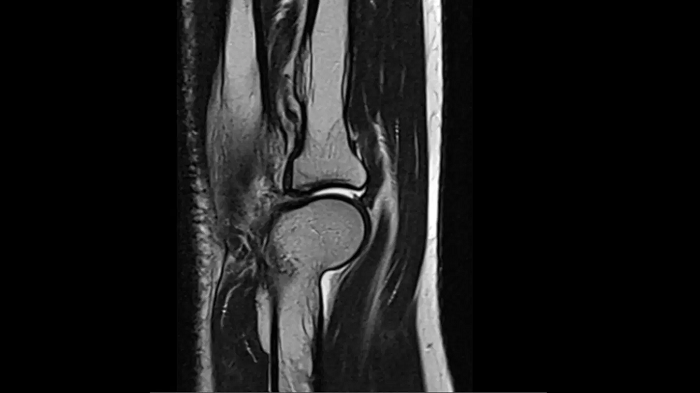

Knee

PD TSE Fat Sat with Deep Resolve and Simultaneous Multi-Slice

For clear imaging of the knee, outstanding fat suppression and performance are possible. Integrating the influence of Deep Resolve with the established Simultaneous Multi-Slice technique.

SMS 2 | Deep Resolve Gain & Sharp

0.4 x 0.4 x 3.0 mm2

TA 2:56 minutes

MAC-ID: 7aaaa0198.

MAC-ID: 7aaaa0198. Image Credit: Siemens Healthineers

For clear imaging of the knee, brilliant fat suppression and performance are possible. Integrating the influence of Deep Resolve with the proven Simultaneous Multi-Slice technique.

0.3 x 0.3 x 3.0 mm2

TA 2:16 minutes

T1 SE

Outstanding T1 imaging of the knee using MAGNETOM Free.Star.

TA 2:54 minutes